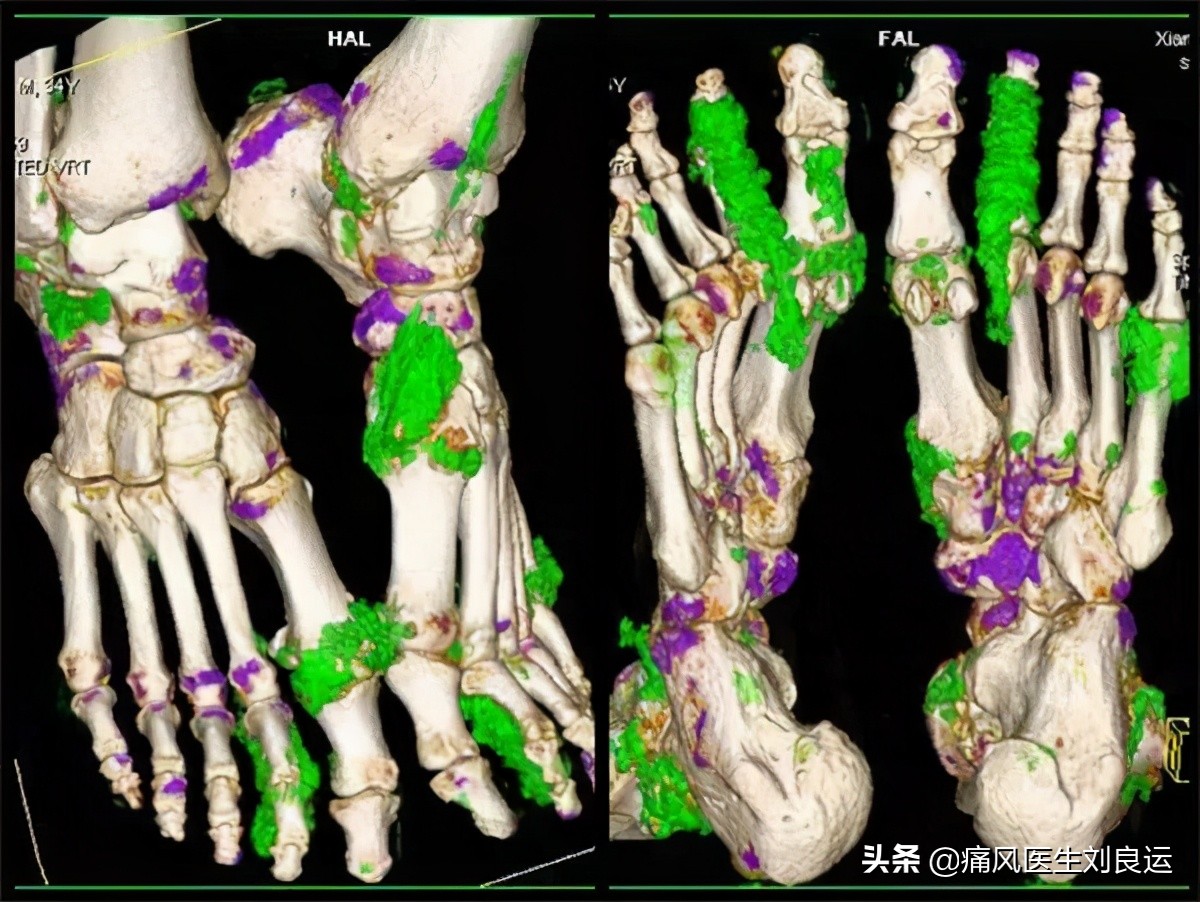

双能CT下痛风性关节炎

其实腱鞘炎的疼痛点是固定不变的,但是痛风性关节炎的疼痛常常会随着病程的加长,疼痛部位增多;还有就是疼痛的性质,痛风的疼痛是红肿热痛,夜间发病较多;而腱鞘炎出现症状与类风湿性关节炎相似,会出现早起晨僵的情况。